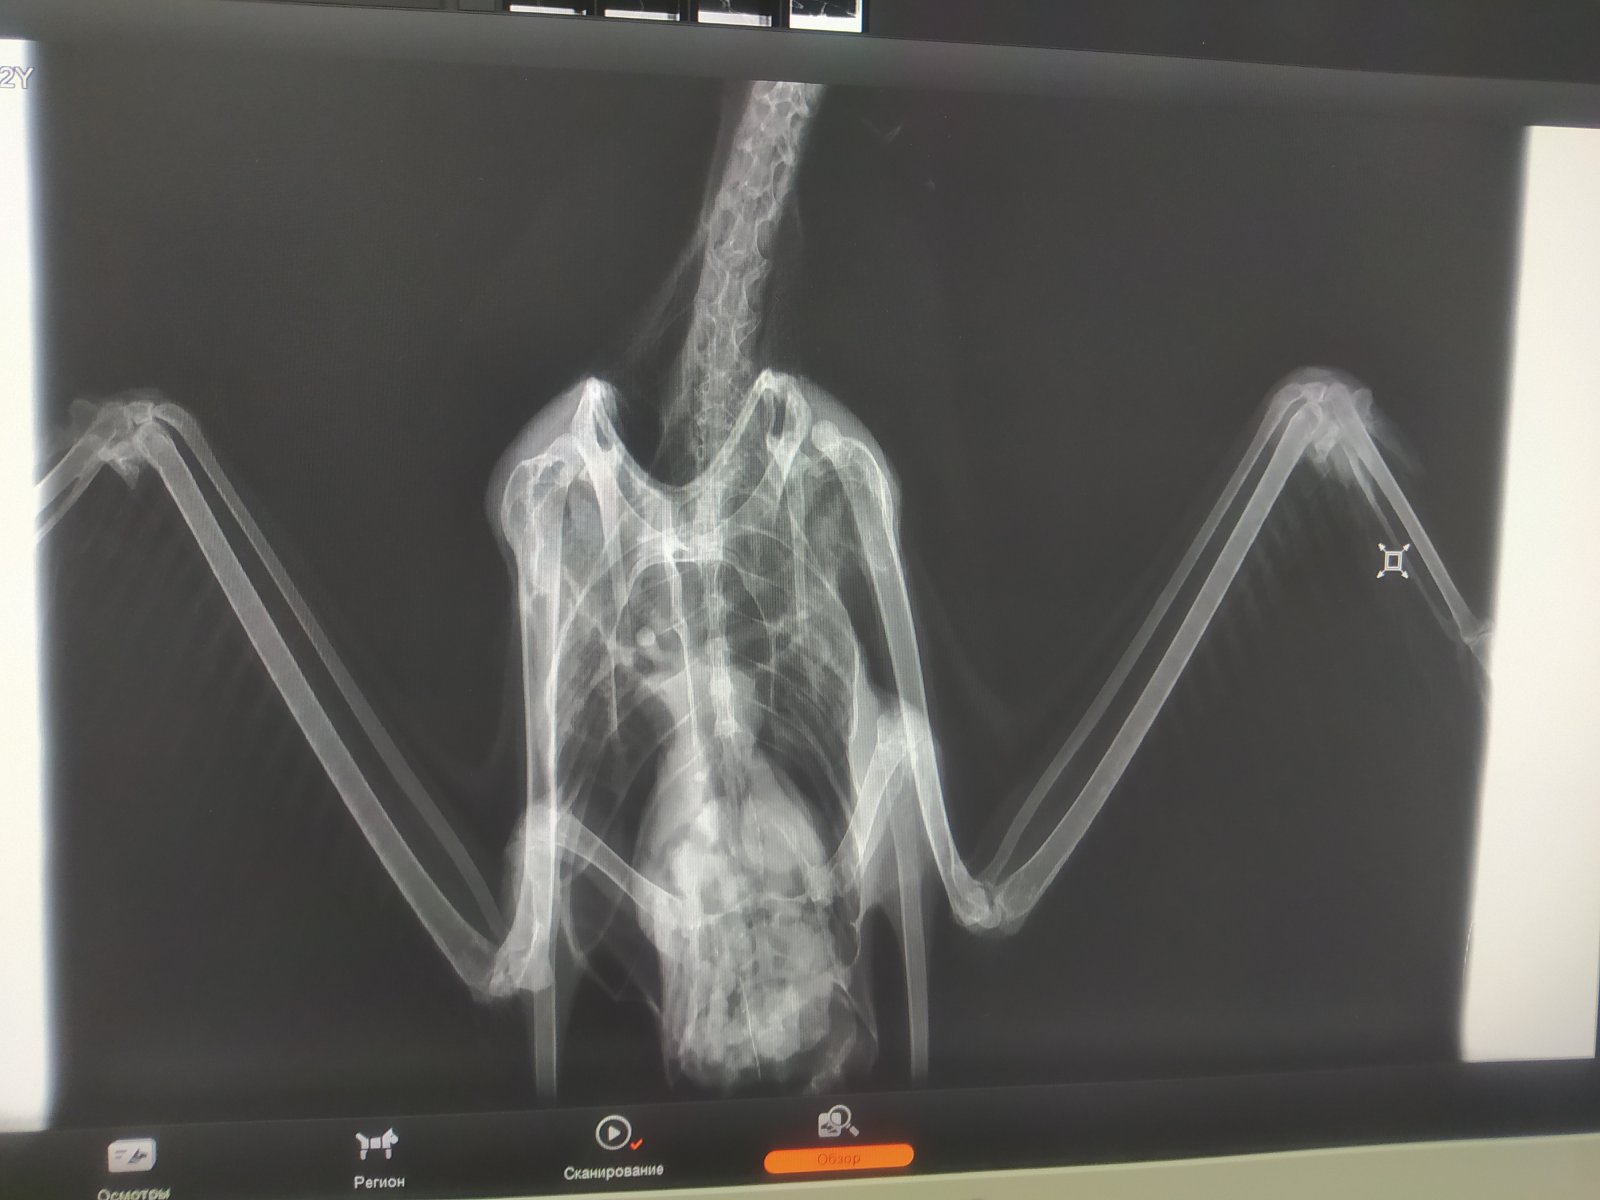

Четрые дня назад на участке нашла птицу, убегает, клюется, самостоятельно ест и пьет. В первый день была покормлена 2 варёными яйцами, все остальные дни только размороженная рыба. Днём гуляет по участку, на ночь убираю в картонную коробку. Думаю это серебристая или средиземноморская чайка. Вес около двух кг. На рентгене переломов не замечено

По чайкам тоже не спец. Но левое крыло не рабочее.от слова совсем.

Короче, с костями птицы все было нормально, оба крыла рабочие, но.. Вот эта вот крохотная металлическая проволока проигнорированная мной на рентгене как артефакт её и убила(

Распорот кишечник, гнойный перетонит, тромб в сердце (скорее всего посмертный)